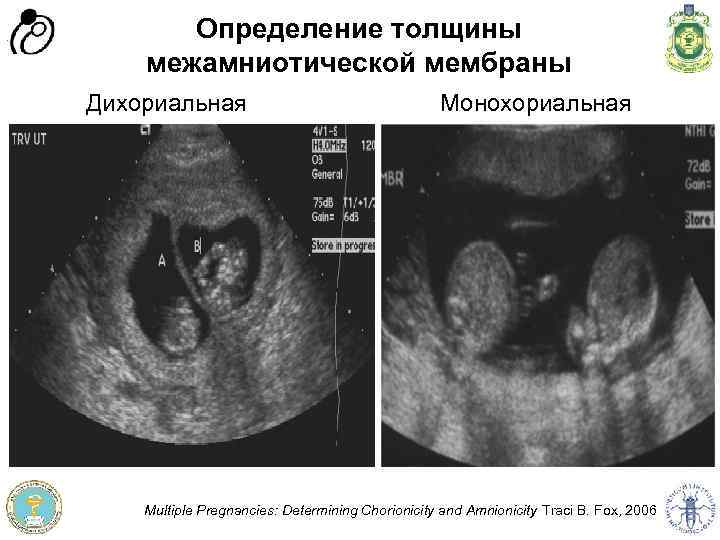

Признак Монохориальная двойня Бихориальная двойня Определение λ- и Тпризнаков Т-признак λ- признак Подсчёт плацент 1 плацента 2 плаценты Определение пола плодов Однополые и разнополые Определение толщины межамниотической мембраны < 2 мм (2 слоя оба амниот. ) > 2 мм (4 слоя: 2 хорион. , 2 амниот. ) Програма доров'я матері та дитини” Швейцарія - Україна Програма “Здоров'я матері та дитини” Швейцарія - Україна Диагностика хориальности в сроке 10 -13 недель

Определение толщины межамниотической мембраны Монохориальная Програма доров'я матері та дитини” Швейцарія - Україна Програма “Здоров'я матері та дитини” Швейцарія - Україна Дихориальная Multiple Pregnancies: Determining Chorionicity and Amnionicity Traci B. Fox, 2006